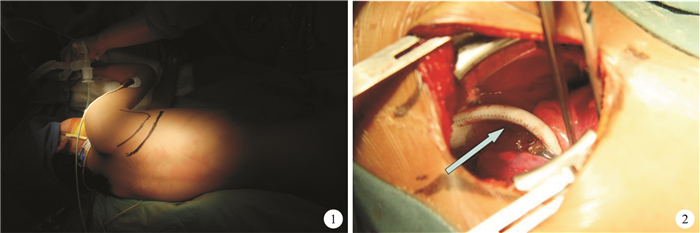

所有患者右側或左側臥位行非體外循環下鎖骨下動脈-肺動脈鏈接,經右側或左側后外側切口第4肋間進胸(圖 1),解剖鎖骨下動脈、左/右側肺動脈,根據肺動脈發育情況及患者體重,以直徑4 mm或5 mm Gore-Tex人造血管連接鎖骨下動脈-肺動脈(圖 2),以0.3~0.5 mg/kg肝素抗凝,維持活化凝血時間(ACT)200 s左右,術后第2 d重疊使用阿司匹林(3~5 mg/kg)抗凝,術后第3 d開始單獨使用阿司匹林抗凝,至二次手術前1周停止抗凝。